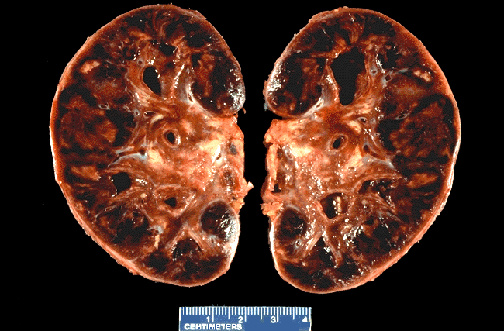

This transplant kidney removed from the recipient is swollen and has global infarction from acute rejection.